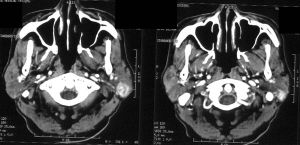

3、CT掃描可清楚顯示腫瘤的大小以及淚乳窩骨質侵蝕。